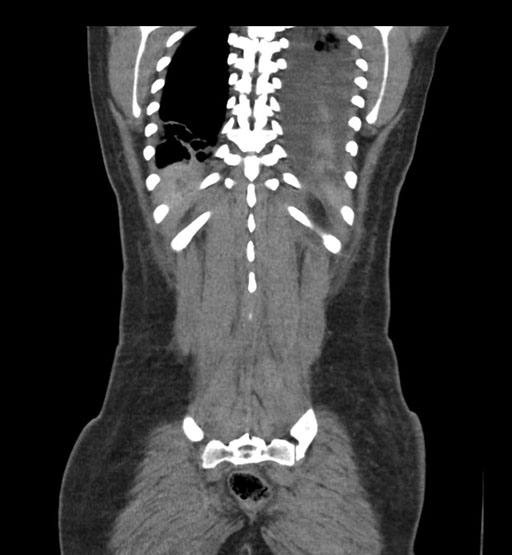

Imaging Analysis

Look through the patient's CT scan to identify any areas of concern for the necessary procedure.

Coronal Arterial

Coronal Venous